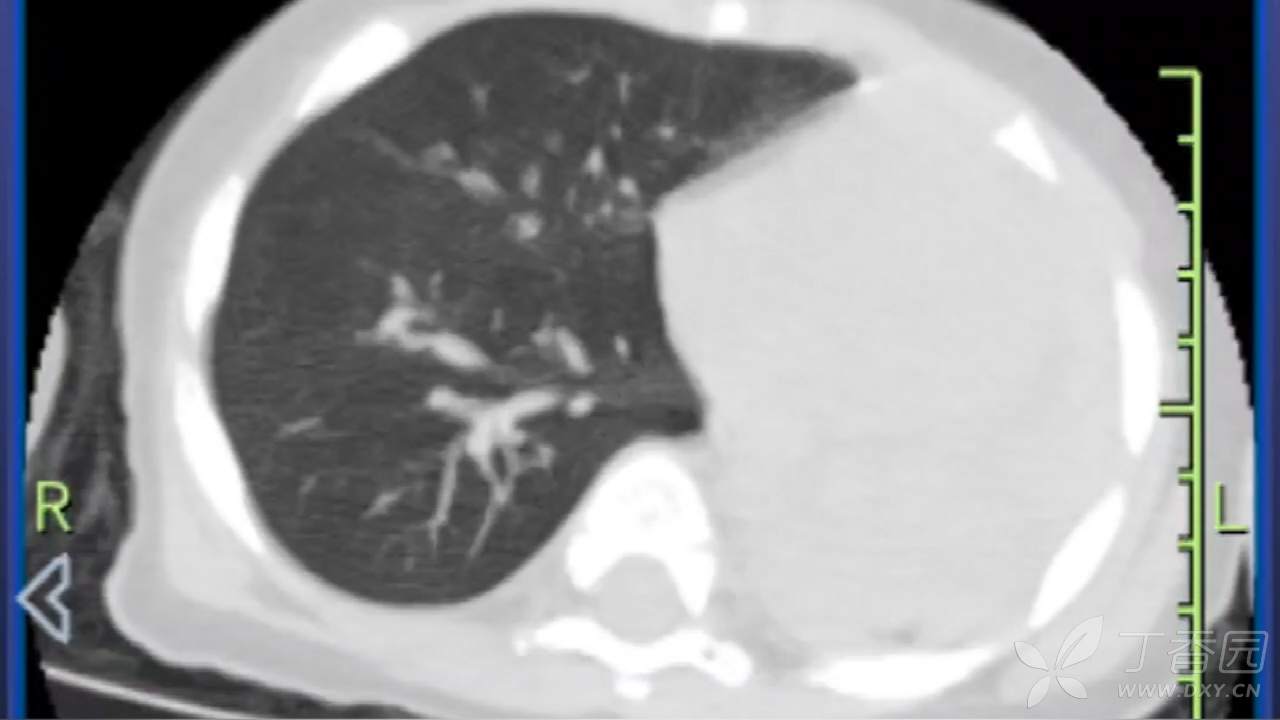

全白的左肺

考虑「呼吸衰竭,支气管肺炎」,予「头孢他啶静滴抗感染,甲强龙抗炎平喘,雾化等对症治疗」,患儿病情进行性加重,出现呻吟、面色苍白、精神反应差,面罩吸氧 5L/min下血氧饱和度维持 90% 左右,为进一步诊治,120 转来我院,急诊拟「重症肺炎、呼吸衰竭」收住 ICU。

8.23 肺部 CT 如图: